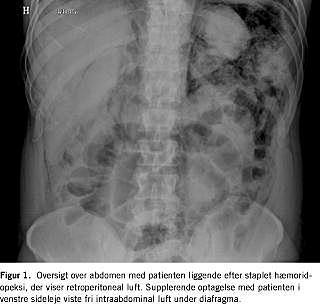

En 38-årig, tidligere rask mand fik foretaget elektiv staplet hæmoridopeksi som følge af blødende grad IV-hæmorider. Staplingen blev foretaget med Ethicon PPH03 med patienten i stensnitleje [2]. En forudgående rektoskopi viste normale forhold. Stapleren indeholdt en fyldig og intakt vævsring uden patologiske forandringer. Blødning fra staplerlinjen blev elkoaguleret med diatermi tillige med to puder hæmoridvæv, og der blev anbragt en spongostanmèche inden for anus. Patienten klagede få timer postoperativt over smerter i nedre abdomen og i højre del af scrotum, hvor der var emfysem. På mistanke om lækage blev der påbegyndt intravenøs antibiotikabehandling med gentamicin, penicillin og metronidazol. På den anden postoperative dag klagede patienten fortsat over smerter, som var morfikakrævende. Et røntgenbillede af thorax viste fri luft intra- og retroperitonealt. På tredjedagen postoperativt var abdomen distenderet med tympanisme i alle fire kvadranter. På en røntgenoversigt over abdomen sås større mængder fri retroperitoneal og subdiafragmatisk luft (Figur 1 ). Antibiotikabehandlingen blev suppleret med ilttilskud på 5 l/min. Ved en akut anorektoskopi sås en normalt udseende anus uden udfald og med staplerlinjen beliggende 6-7 cm over den anokutane overgang uden påviselige defekter eller nekrotiske partier. På den fjerde postoperative dag blev der udført en computertomografi, som viste fri luft omkring rectum, langs funiklen, strækkende sig retroperitonealt og videre op i mediastinum posterior. Desuden var der en mindre mængde fri luft intraperitonealt i krøs og i lille sæk. På den femte postoperative dag forlangte patienten at blive udskrevet. Et kontrolrøntgenbillede af thorax og abdomen på den sjette postoperative dag viste ingen fri luft i peritoneum og betydelig regression i retroperitoneum. Patienten var i hele forløbet afebril og relativt upåvirket, men B-leukocytter og P-C-reaktivt protein var forhøjede.